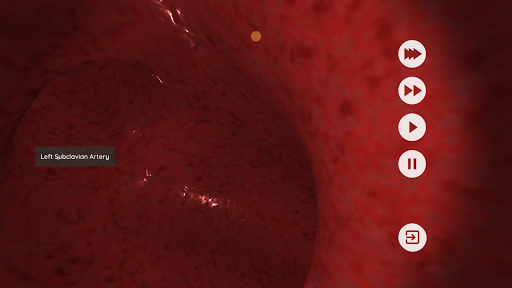

Anatomyou VR est une application mobile éducative qui présente l'anatomie humaine à l'utilisateur d'une manière immersive.

En utilisant la réalité virtuelle, vous serez capable de naviguer le long des structures anatomiques, devenant une partie de l'anatomie humaine: circulatoire, respiratoire, digestive, urinaire, lacrymale et système reproducteur féminin.

Ceci est une version récemment rénovée d'Anatomyou VR. Les fonctionnalités incluent: - Anatomie humaine plus réaliste, améliorant les modèles et les textures. - Meilleure interaction de l'utilisateur en mode VR et en mode plein écran. - Des menus et des images entièrement rénovés permettent une navigation intuitive. - Contenu clinique supplémentaire validé par nos experts. - Les utilisateurs précédents doivent accepter certaines autorisations (GoogleVR SDK). Nous avons mis beaucoup d'efforts dans cette mise à jour, j'espère que vous l'apprécierez!